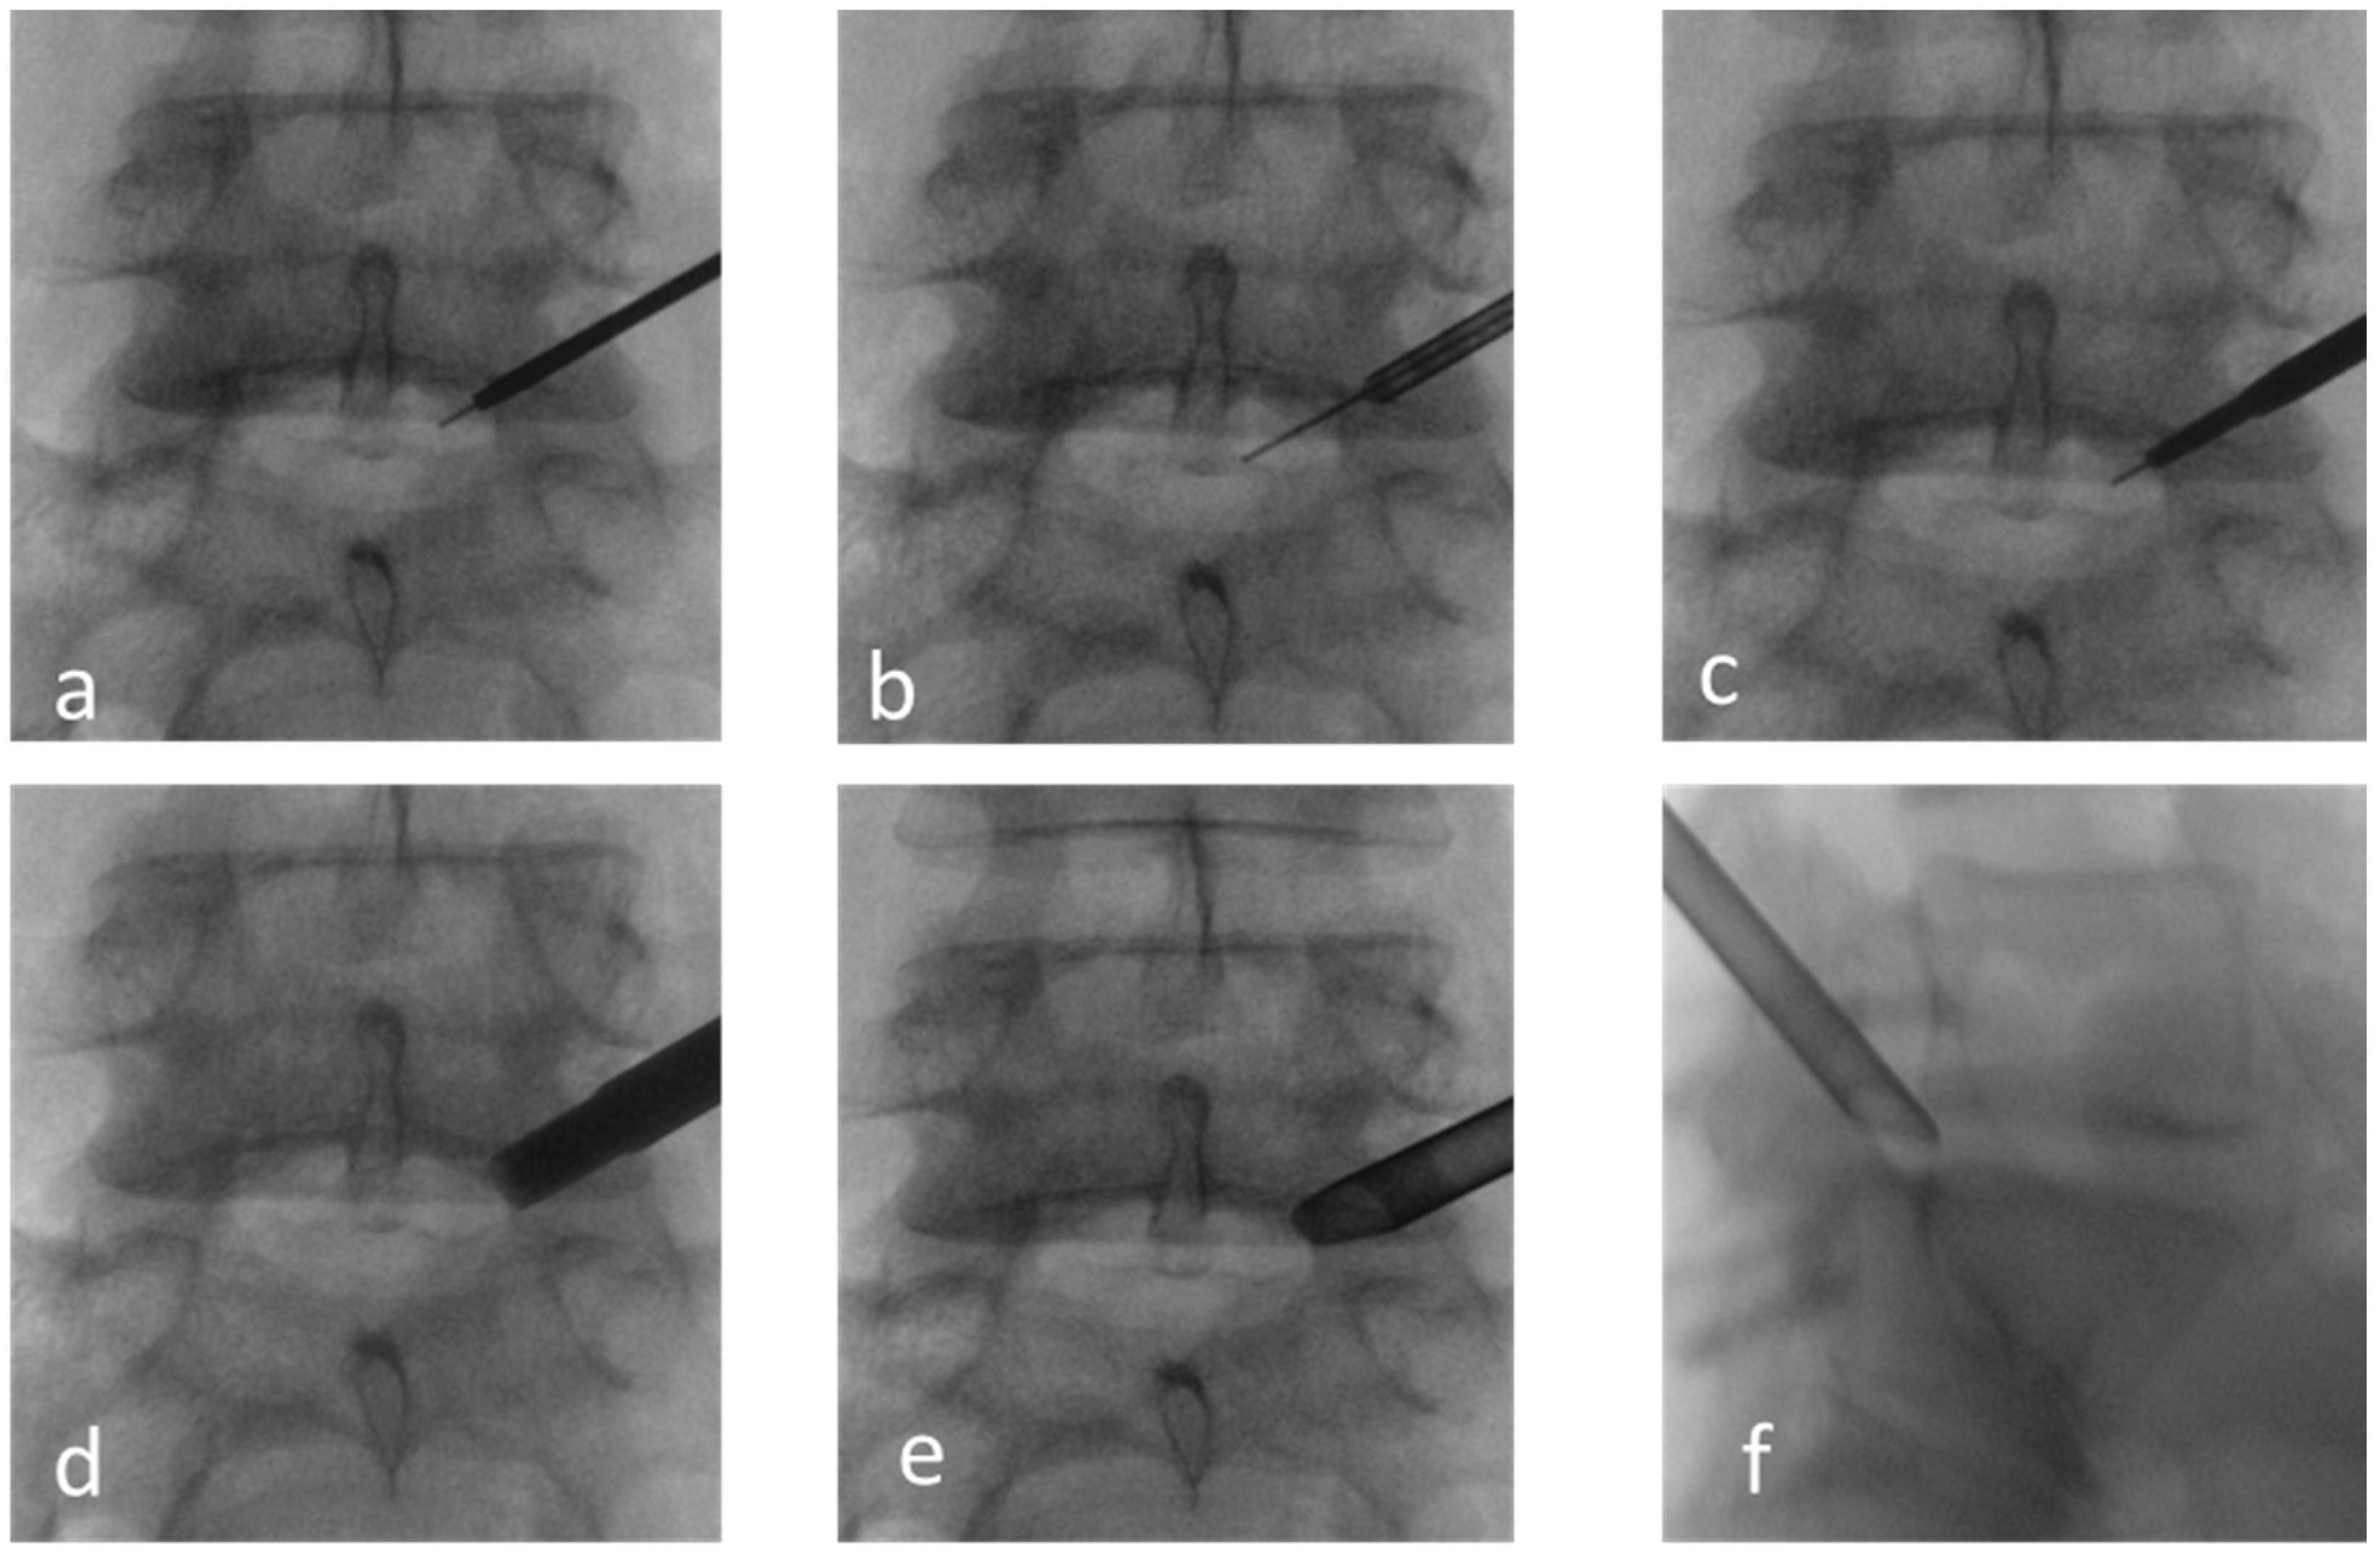

2. Materials and Methods

2.3. Surgical Data